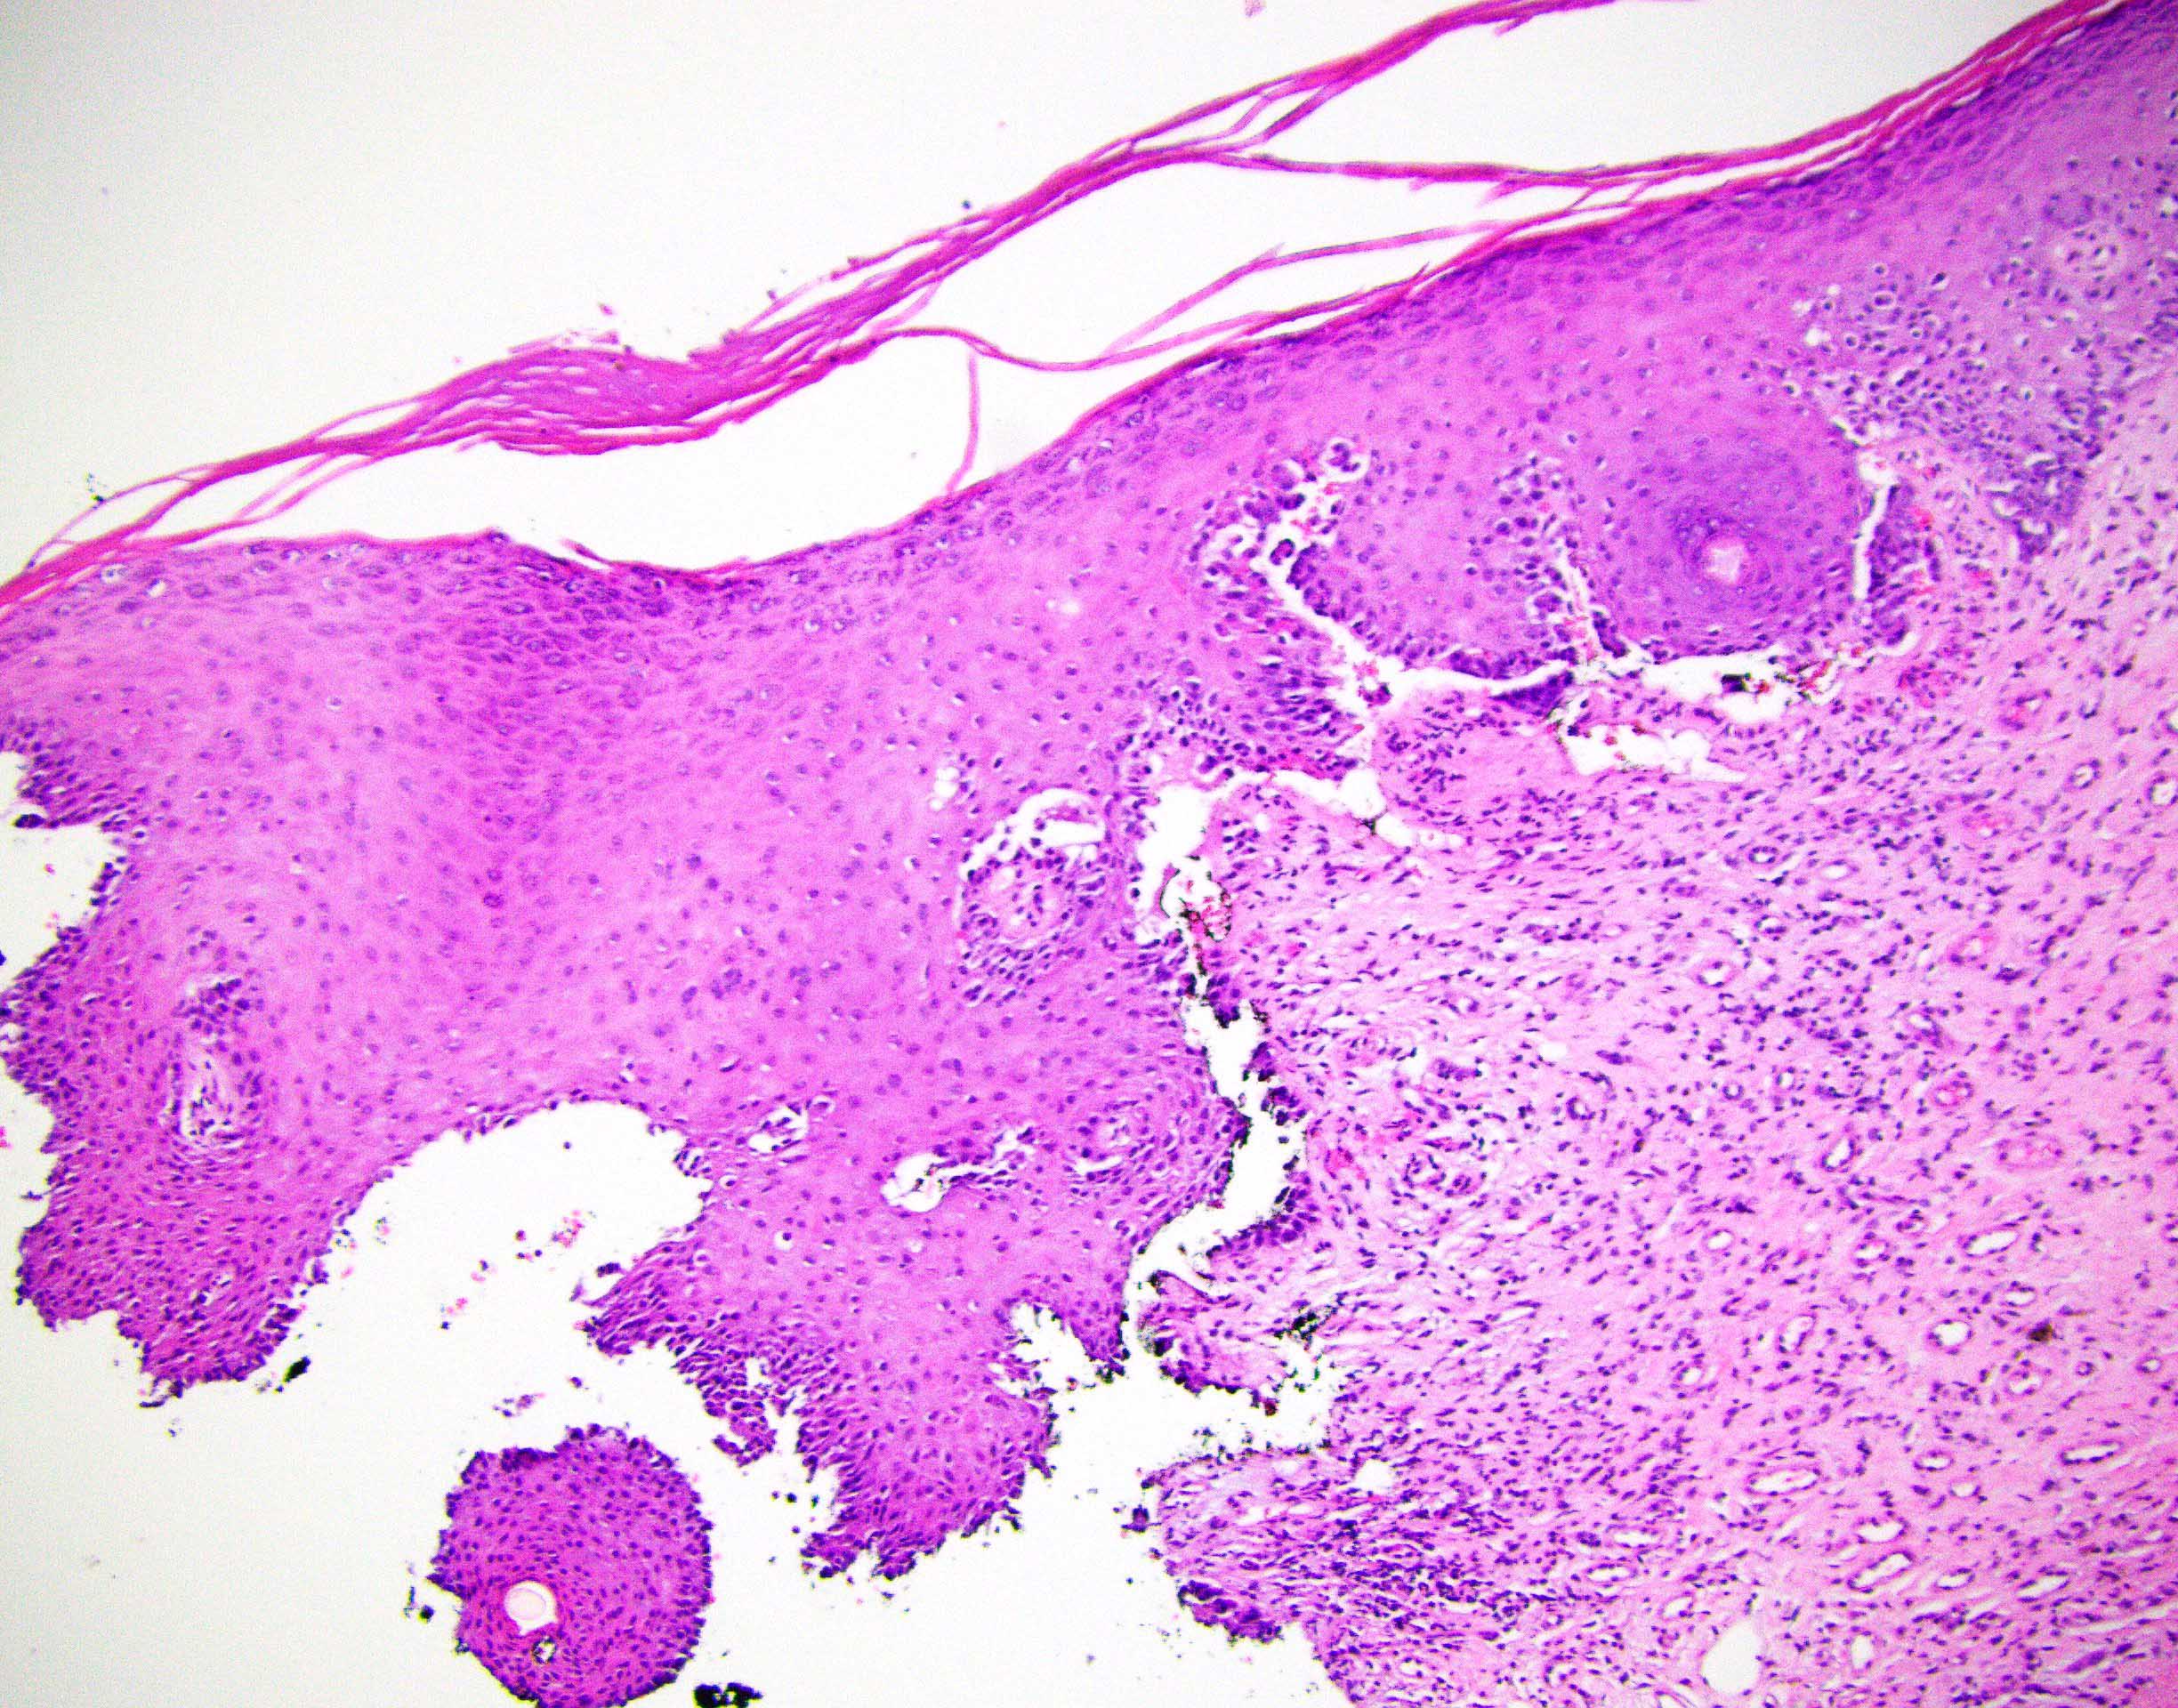

Microscopic (histologic) description

- Paget cells are enlarged polygonal epithelial cells with abundant pale cytoplasm, large nuclei and small to prominent nucleoli

- Intracytoplasmic mucin is frequently present

- Intracytoplasmic melanin pigment may be present (rare)

- Rarely, gland formation may be seen

- Predominantly located in the basal and parabasal portions of the squamous epithelium

- Extends upward as single cells or in small clusters

- Commonly involves the epithelium of skin adnexa

- Basal layer keratinocytes are preserved but may appear compressed by the tumor cells (Histopathology 2006;48:723)

- Prominent host inflammatory response in the superficial dermis is frequently seen

Microscopic (histologic) images

Contributed by Priya Nagarajan, M.D., Ph.D. and Lucy Ma, M.D.